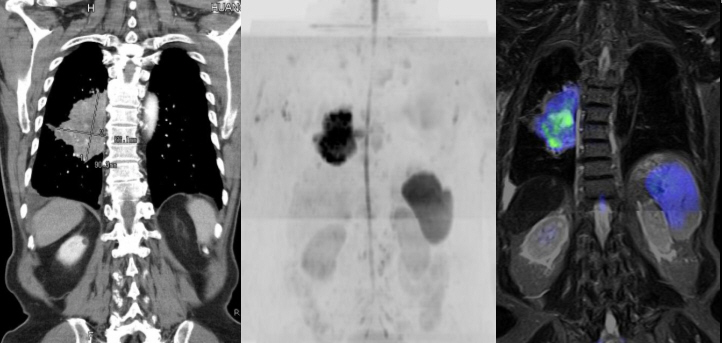

● 提供全身性腫瘤偵測新技術 – 分子擴散加權影像。

磁振造影主要對於各種腫瘤及軟組織各種疾病之診斷,均能提供絕佳的對比影像。臨床上,磁振造影對實質器官如:腦神經系統、肌肉骨骼系統、脊椎軟骨、甲狀腺、肝、膽、脾、腎、胰、腎上腺、生殖器官 (膀胱、子宮、卵巢、輸精囊、攝護腺)及乳房,有絕佳的診斷價值。正子攝影可以提供全身掃描影像,主要是偵測惡性腫瘤及轉移,適用於頭頸部腫瘤、鼻咽癌、肺癌、乳癌、胰臟癌、大腸癌等。另外正子斷層掃描亦具有輻射線;而磁振造影則無。